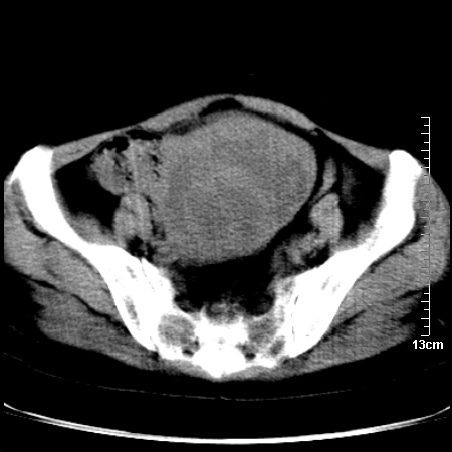

术前的疏忽,手术前诊断阑尾炎,但是没有常规做b超,导致术后1周检查发现 1。实性包块?2。腹腔术后脓肿?

病史:病人一周前诊断阑尾炎,未做b超,手术发现阑尾化脓,(没有留意有无包块),术后1周病人发热,血象:1.6万,做b超发现,随ct检查,上传图片

巨大囊实性包块,边界大部尚清楚,不太像脓肿的表现。应该做个增强检查除外盆腔肿瘤。

脓肿可能性大. 因回盲部区域化脓性兰尾切除残端感染改变征像与实性肿块关系密切.肿块上界至右下腹,下界至盆腔膀胱上缘, 如果是实性肿块在兰尾术中可能就会发现. 所以术后一周病人高烧, 白细胞增高,临床表现支持脓肿.

盆腔一边界大部份清晰囊实性肿块,其周腹脂未见确切异常,其一端与右侧附件相连。考虑右侧附件肿瘤。

如果能进行肠道准备就好了!盆腔内巨大囊实性包块,右前缘与周围肠管分界不清,病灶内前部的气体是否为肠管内气体形成的假象不能确定。

这么大一包快手术当中没有发现?值得怀疑!结合化脓性阑尾炎病史,首先考虑脓肿!不排外附件来源的肿瘤,建议增强扫描!!